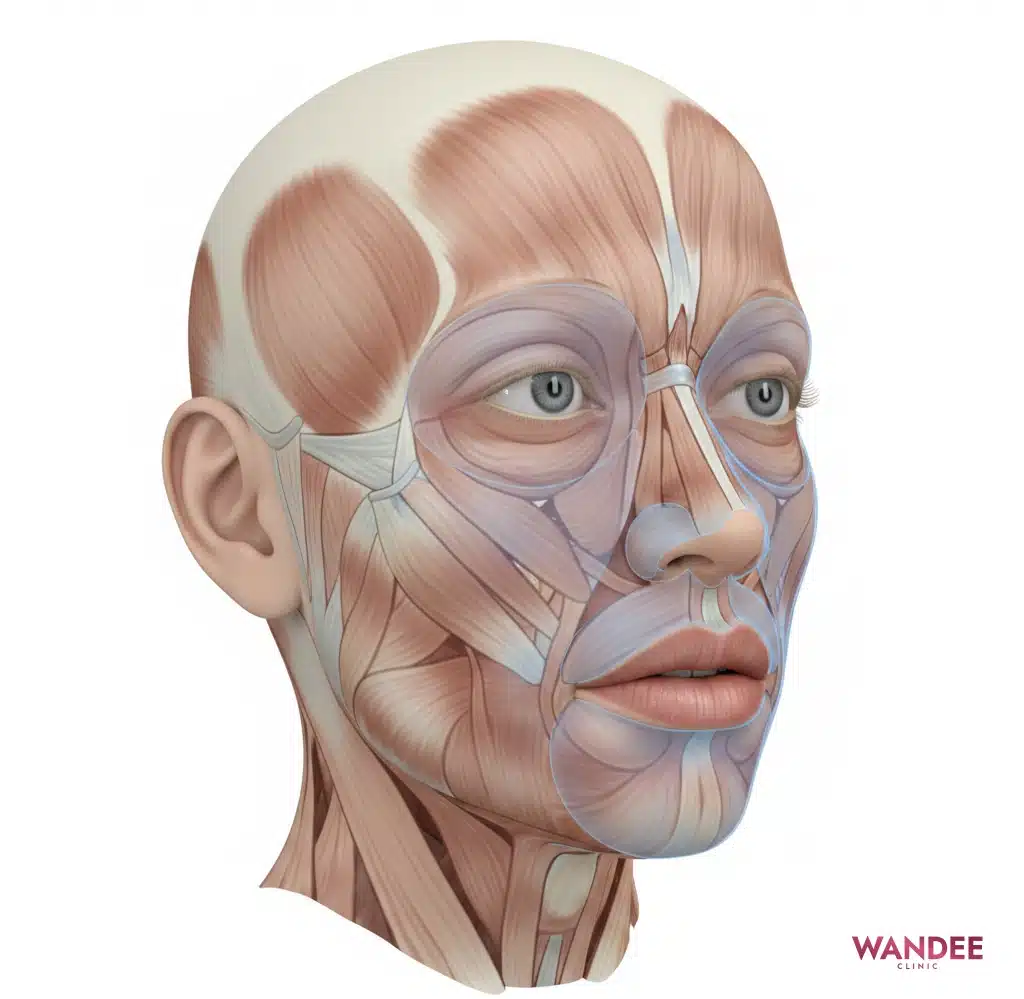

ฟิลเลอร์ที่ใช้กันแพร่หลายคือ Hyaluronic Acid หรือ HA ซึ่งเป็นสารที่ร่างกายมีอยู่แล้วตามธรรมชาติในผิว จุดเด่นของ HA คือจับน้ำได้ดี จึงให้ความชุ่มชื้นและเพิ่มวอลลุ่มได้

เมื่อทำเป็นฟิลเลอร์ HA จะถูกออกแบบให้เป็นเจล เพื่อให้อยู่ทรงในชั้นที่ฉีด คุณสมบัติอุ้มน้ำยังมีอยู่ ทำให้บางคนรู้สึกว่าช่วงแรกดูฟูได้ โดยเฉพาะตำแหน่งที่ผิวบางหรือมีพื้นที่จำกัด

ถ้าอยากเข้าใจภาพรวมว่าฟิลเลอร์อยู่ชั้นไหนและทำงานอย่างไร อ่านต่อได้ที่ ฟิลเลอร์ทำงานใต้ผิวยังไง

ลองนึกภาพว่า HA เป็นโครงสร้างที่ดึงน้ำเข้ามาเก็บไว้รอบ ๆ ตัวเจล เมื่อมีน้ำมาอยู่ในบริเวณนั้น ปริมาตรโดยรวมจะเพิ่มขึ้นเล็กน้อย ทำให้ดูฟูขึ้นได้ โดยเฉพาะช่วงที่ร่างกายยังมีการตอบสนองหลังฉีด

ตำแหน่งที่ผิวบางและมีพื้นที่จำกัด เช่น ใต้ตา มักเห็นการบวมชัดกว่า เพราะบวมเพียงเล็กน้อยก็สะท้อนแสงจนดูฟูได้ง่าย อีกทั้งบริเวณนี้มักไวต่อการคั่งของเหลว ทำให้บางคนรู้สึกว่าบวมอยู่นานกว่าโซนอื่น

ร่องแก้มมักบวมแบบแน่น เพราะเป็นโซนที่มีการขยับจากการยิ้มและการเคี้ยว ส่วนปากมีเส้นเลือดและเนื้อเยื่ออ่อนมาก จึงบวมได้ง่ายเช่นกัน